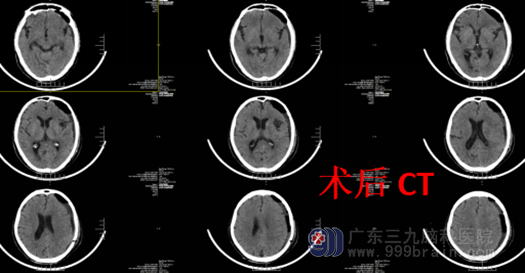

经过医生与家属沟通解释到:“全麻成功,取仰卧位,患者头部右转,纵向小切口,颅骨钻孔;硬脑膜形切开后,见暗红色血液湧出;以生理盐水进行反复冲洗血肿腔,直至灌洗液清亮,留置术腔引流管,手术结束。”外十科行“左侧额颞顶部慢性硬膜下血肿钻孔引流术”,手术进行得非常顺利,术后的容爷爷恢复顺利,也没有出现后遗症,还能自己走路散步了。